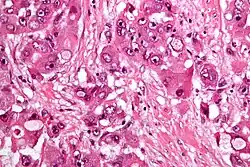

High mag.

The histopathology of FLC is characterized by laminated fibrous layers, interspersed between the tumor cells. Cytologically, the tumor cells have a low nuclear to cytoplasmic ratio with abundant eosinophilic cytoplasm.[1] Tumors are non-encapsulated, but well circumscribed, when compared to conventional HCC (which typically has an invasive border).